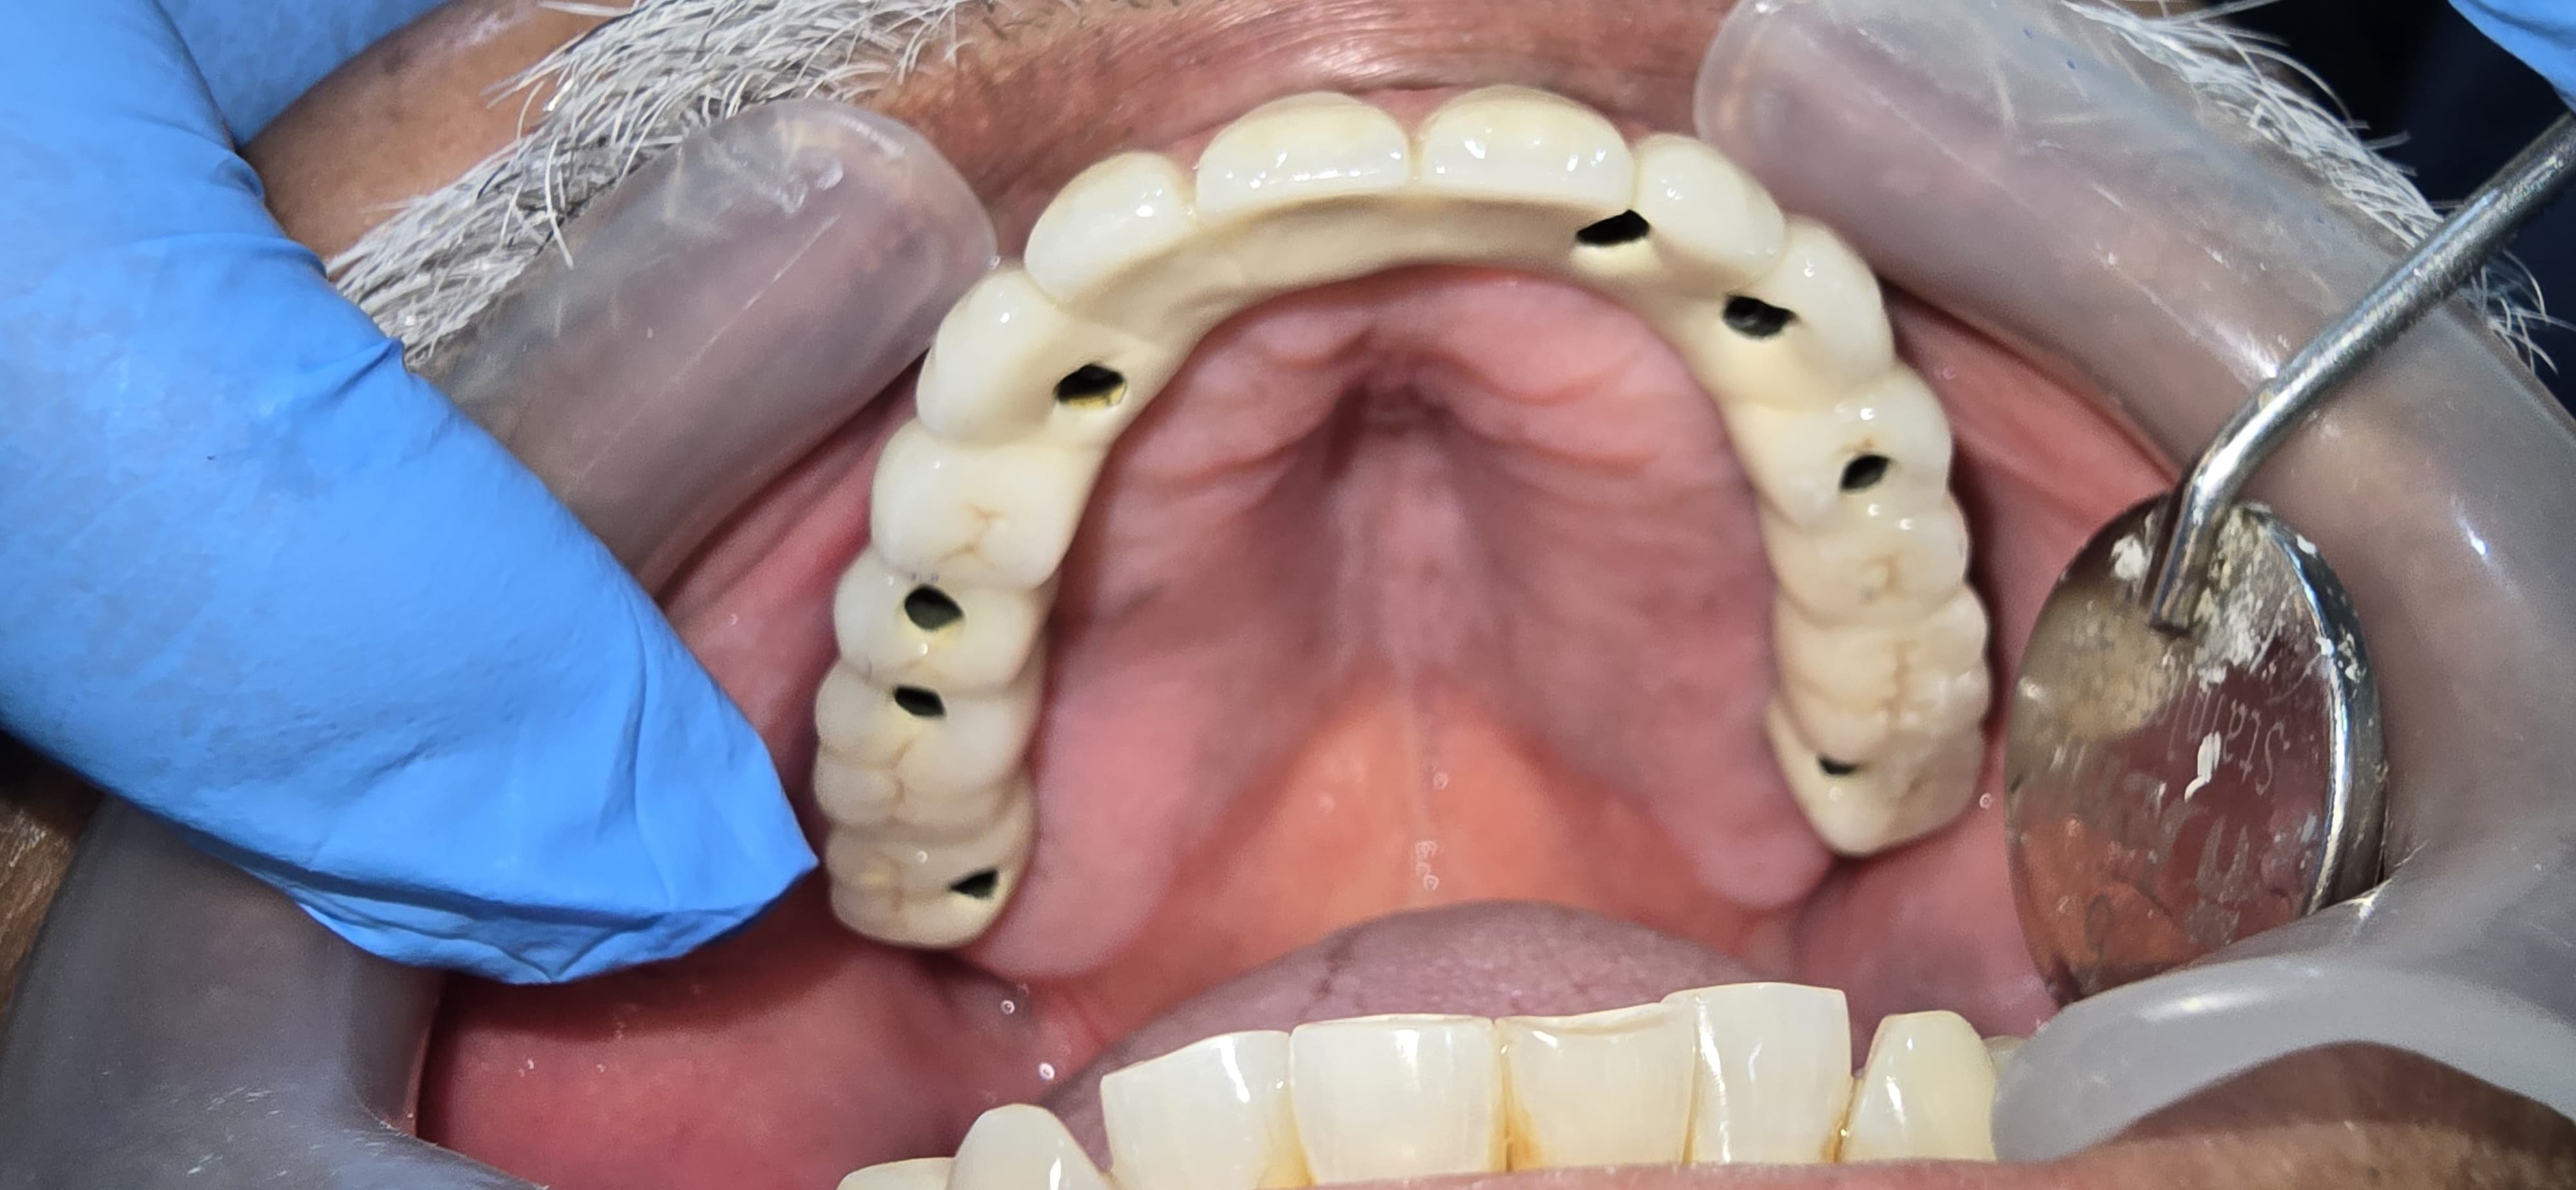

Full Mouth Implant Case

Full Mouth Implants with all Ceramic Crowns